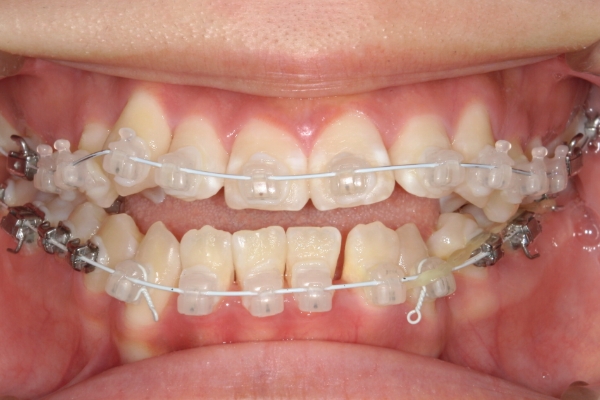

BEFORE

治療前

PROCESS

3か月

AFTER

治療後

骨格的に下あごが前下方に長いことが原因で、受け口、開咬(前歯が当たらない)の症状がでていました。また下あごが右にずれており、その影響で上下の歯列正中(真ん中)の大きなずれも生じていました。顎変形症手術も選択肢の一つでしたが、患者さまの希望もあり、下顎左側小臼歯の抜歯をして通常の歯列矯正で治療をしました。

治療後は、前歯、奥歯の噛み合わせが整い、上下の歯列の真ん中が一致しました。歯列全体のアーチも安定し、機能面・審美面のどちらも大きく改善されました。